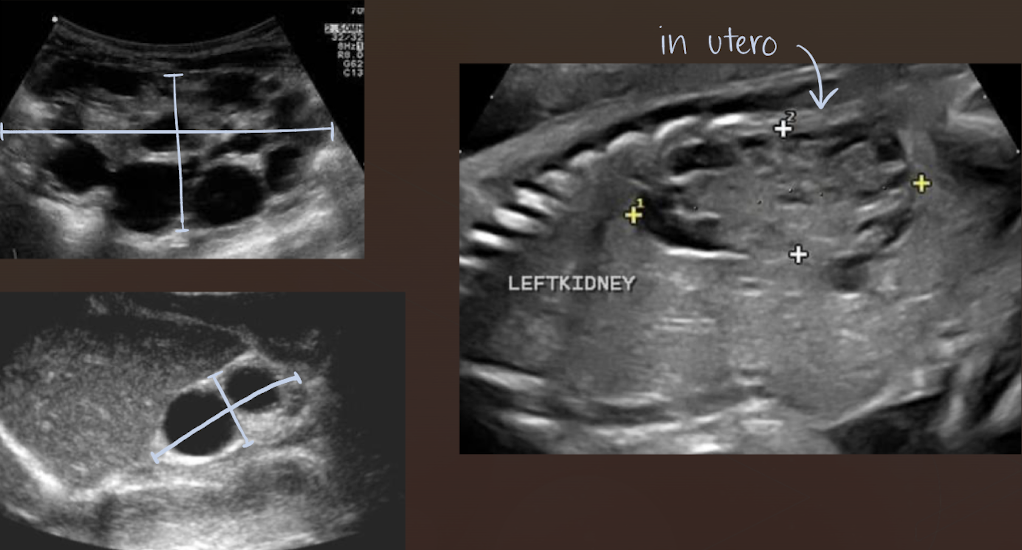

autosomal recessive polycystic kidney disease (ARPKD)

aka infantile polycystic disease

rare disorder caused by gene located on chromosome 6

4 forms based on age of patient when clinical signs present:

Perinatal, neonatal, infantile, and juvenile

dilation of renal collecting tubules → renal failure and later liver involvement

SONO: autosomal recessive polycystic kidney disease (ARPKD)

enlarged echogenic (cortex and medulla) kidneys with microscopic or small cysts

lack corticomedullary differentiation (can’t tell difference between cortex and medulla)